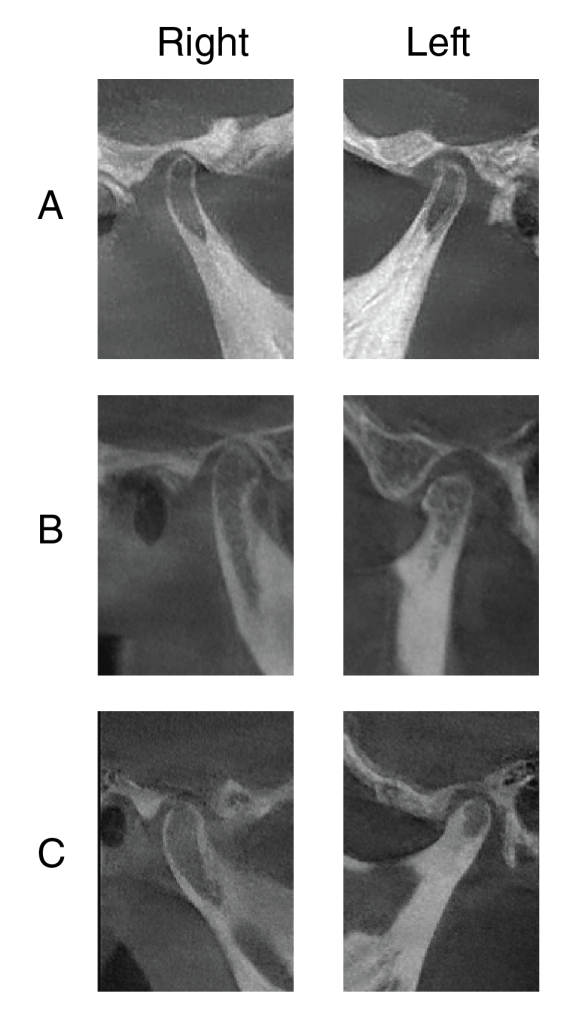

Figure 6: Condyle of a patient with Nemaline Myopathy. Radiographic images show the righ The right and left mandibular condyles of an NM patient (A), a matched open bite (B), and a matched control patient (C). The decrease in size, thinner cortical bone, less trabecular bone, and longer neck differentiate the NM patient from the matched patients.